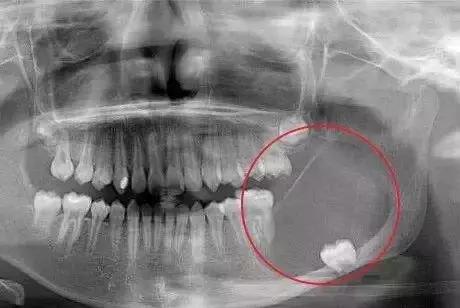

智齿因阻生疑为不明原因神经痛

或可疑病灶牙时

阻生智齿和神经的关系↓

对待这种「骑」在神经上的智齿要以医生建议为主,即使拔也一定要选择微创拔哦。这个危险距离,一锤子下去,神经可就很难保住了。